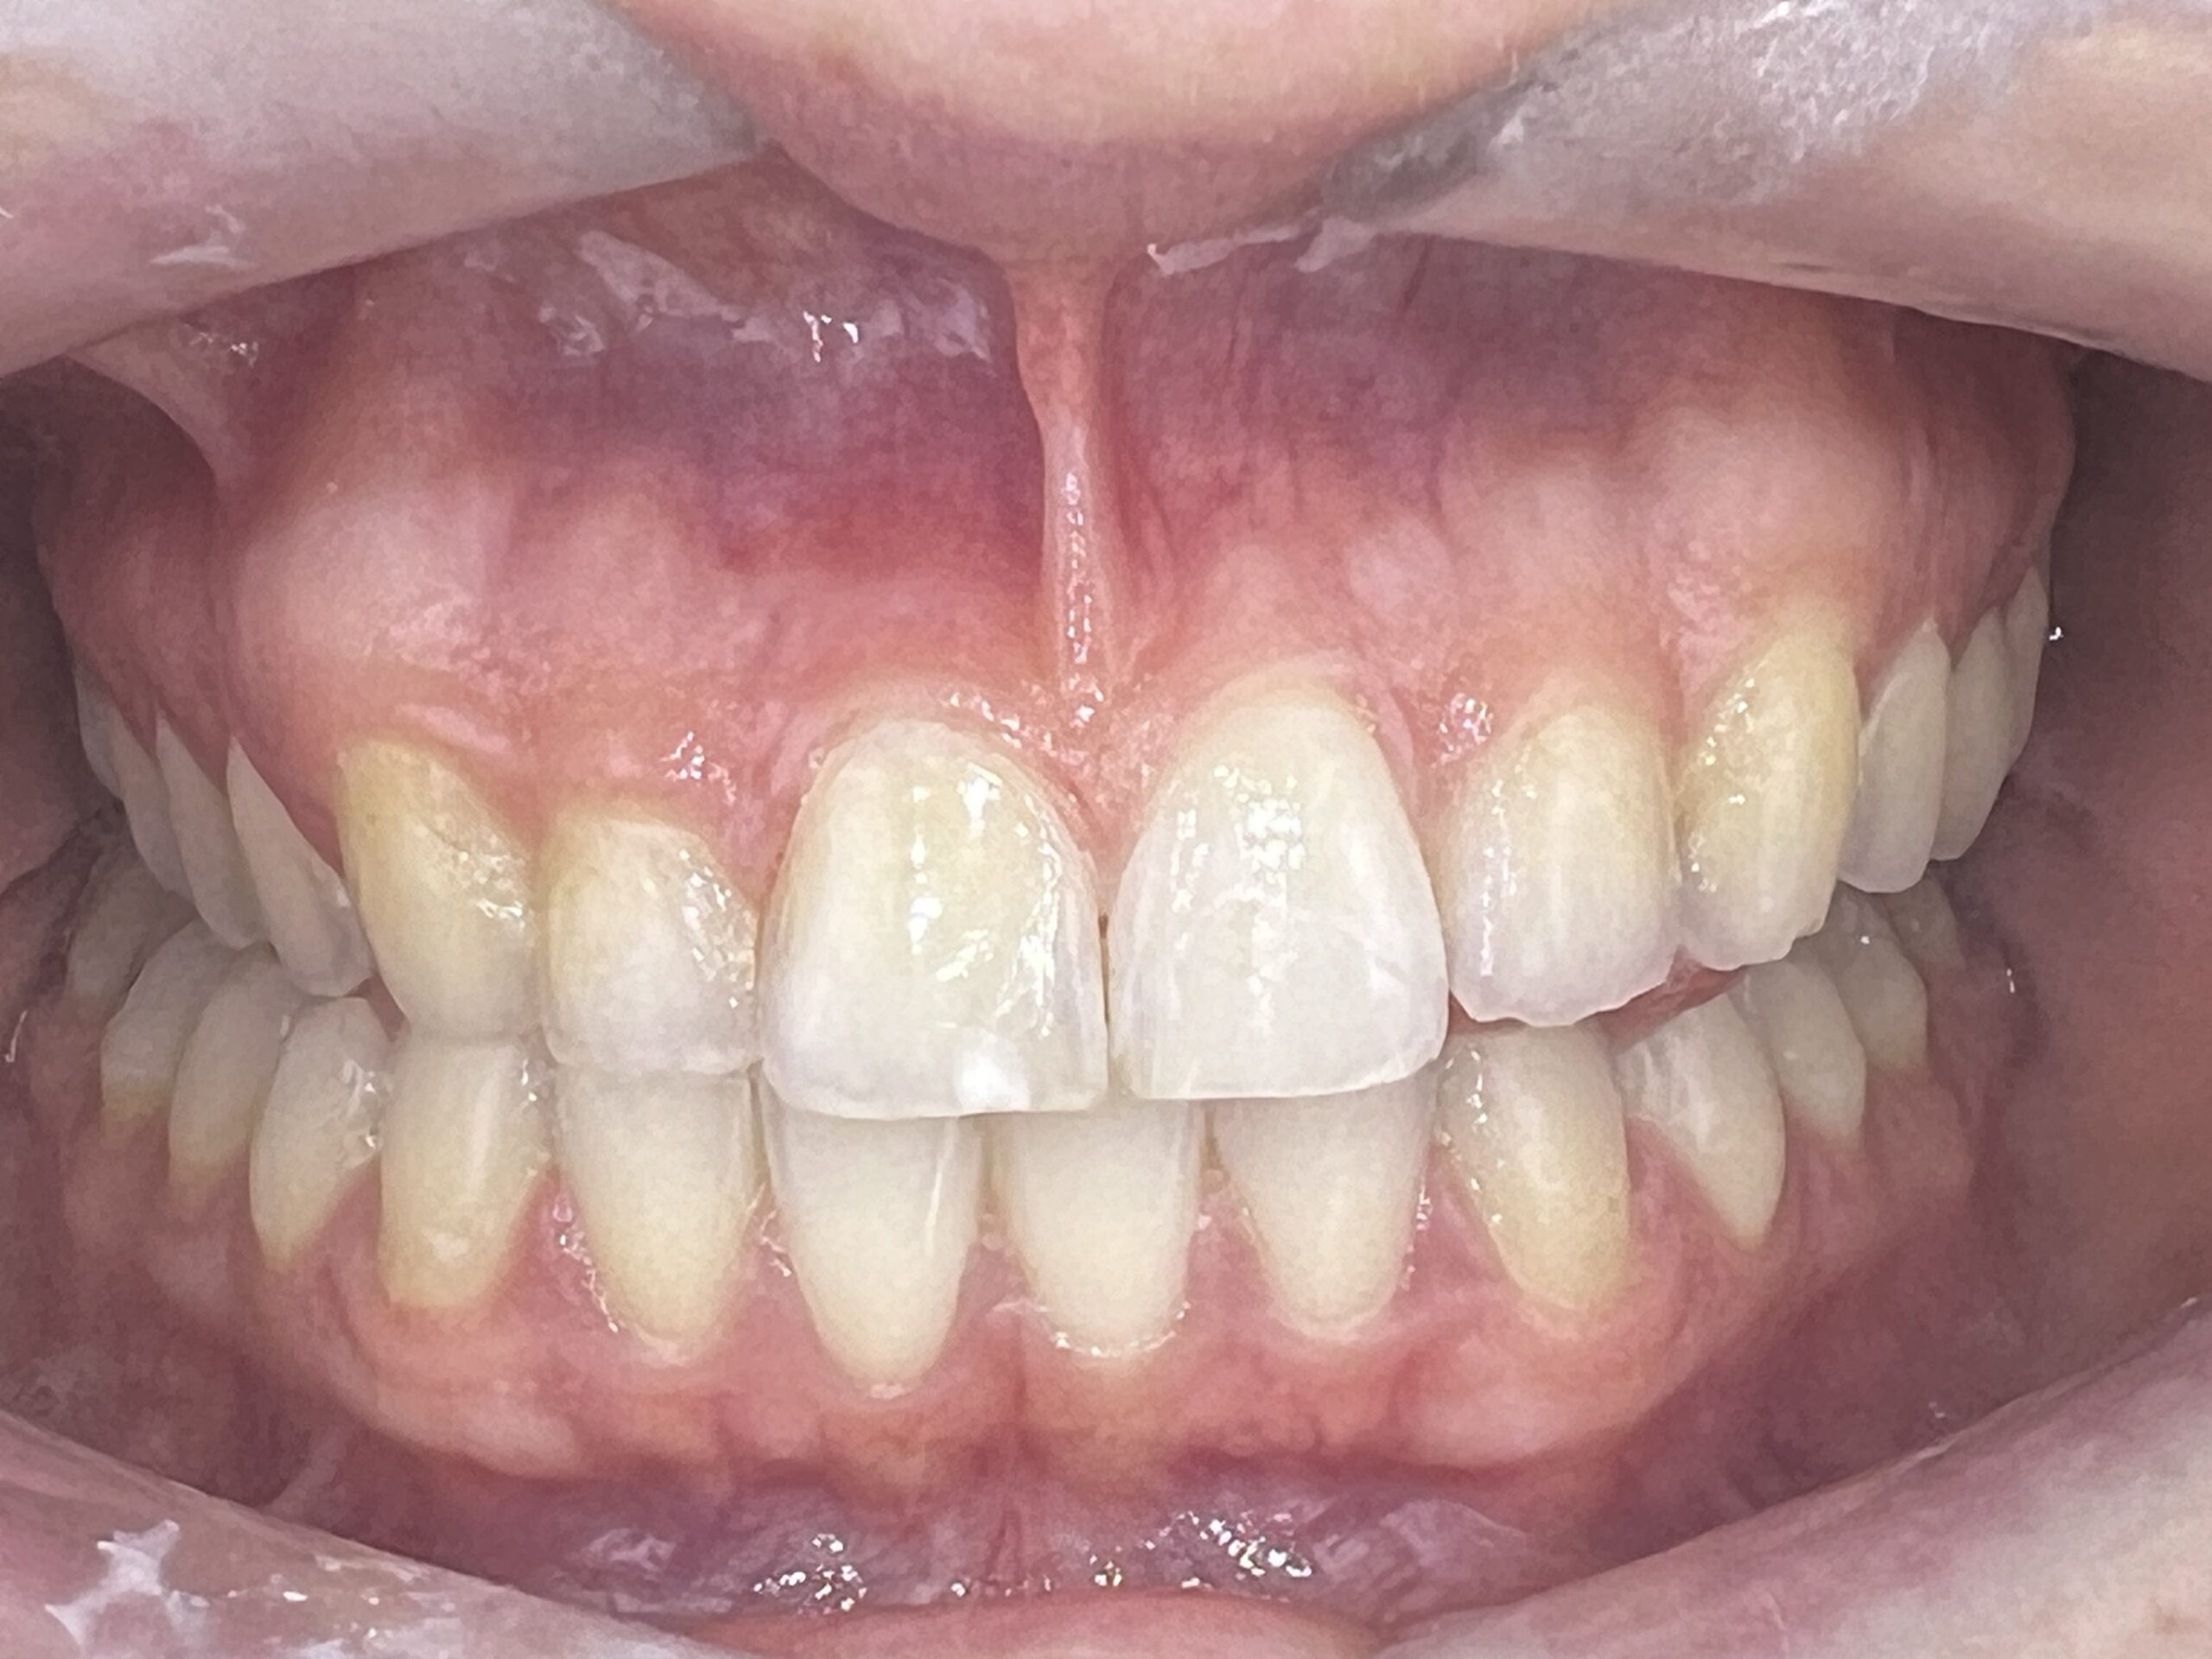

Clinical situation before

Clinical situation after. Bright shade in teeth 12 and Natural in 13 and 23